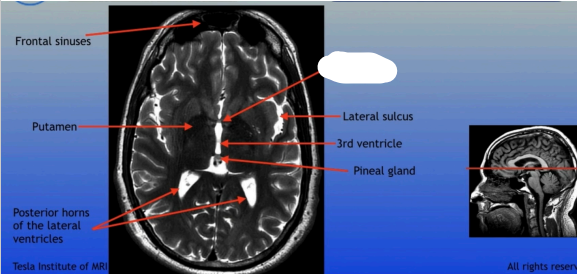

Frontal Sinuses

Putamen

Posterior Horns of the Lateral Ventricles

Central Sulcus

Region of the brain located deep within the lateral sulcus, involved in functions such as emotion processing and self-awareness.

Posterior Horn of Lateral Ventricle

Lateral Ventricle